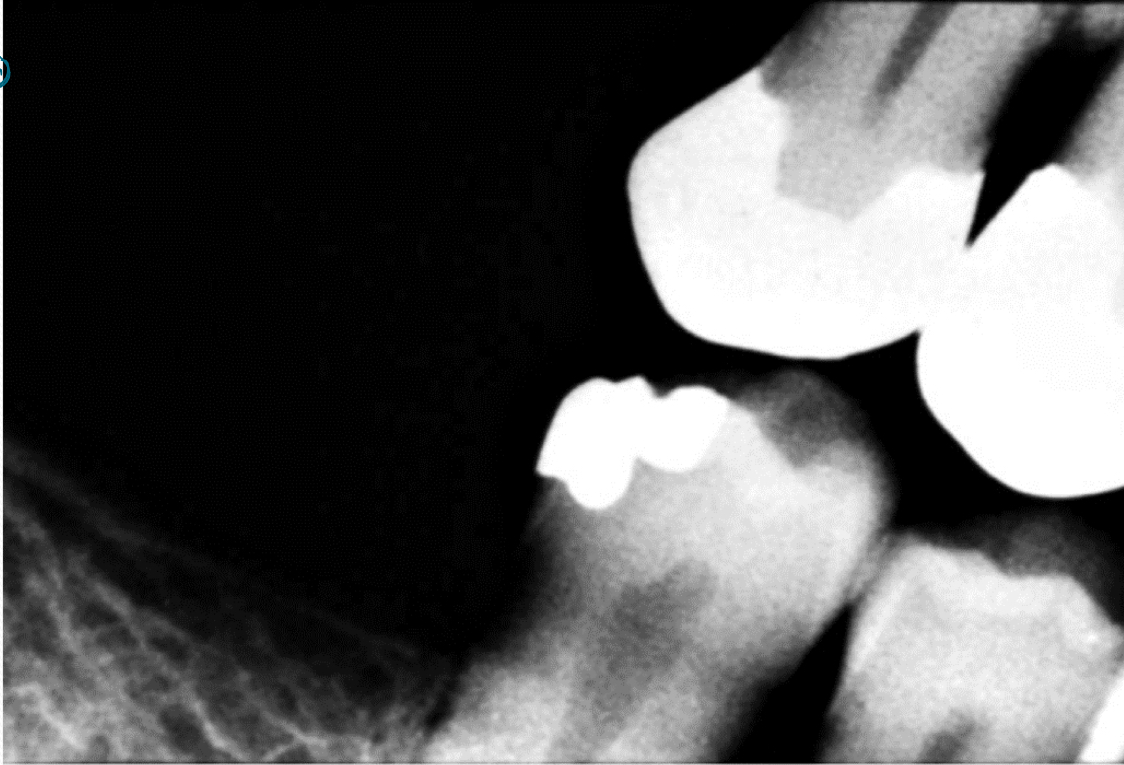

Amalgam restorations